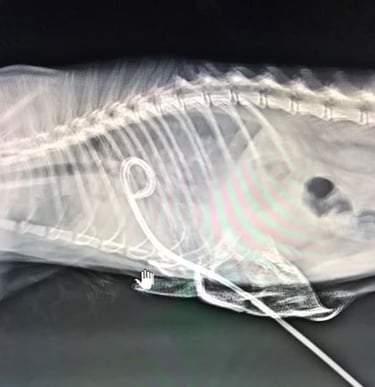

Investigations, including X-ray and ultrasound, revealed a severe pyothorax — a collection of pus and fluid in the chest cavity. Despite repeated aspirations of over 250ml each time, the fluid continued to accumulate, indicating the need for a more advanced intervention.

Our veterinary team employed a pig-tail catheter in the pleural cavity for continuous drainage under sedation and anesthesia. This approach allowed controlled and gentle removal of the infection, helping Mango breathe comfortably and recover steadily.